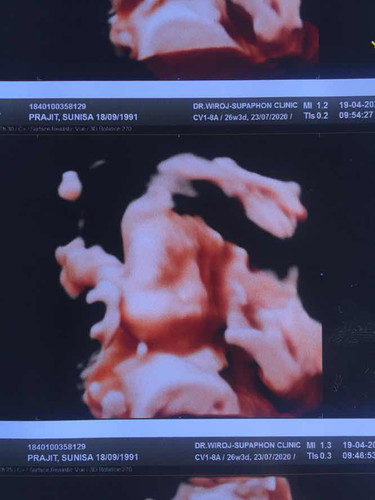

ซาว 3 มิติ

อยากทราบว่า ออกมาแล้วจมูกจะโด่งแบบนี้มั้ยค่ะ ลูกคนแรกค่ะ เลยไม่มีประสบการณ์